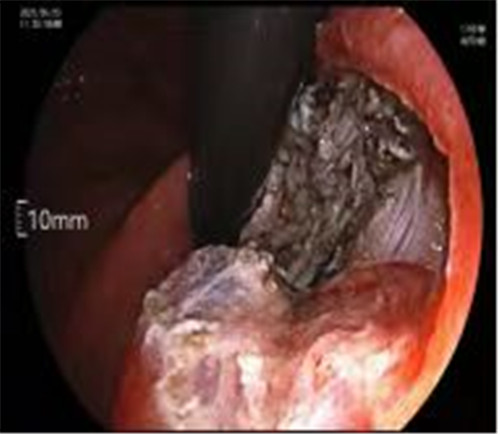

近期病例之一,圖片依次為:胃鏡、超聲胃鏡、ESE術(shù)中、術(shù)后、切下病變。

通過內(nèi)鏡切開瘤體表面粘膜,分離后挖除瘤體,或以消化道全層切除的方法切除瘤體,并在內(nèi)鏡下縫合切口。與傳統(tǒng)手術(shù)相比,該項(xiàng)技術(shù)利用了人體自然通道,不會(huì)破壞人體結(jié)構(gòu),更加微創(chuàng)。不超過3cm向消化道腔內(nèi)生長(zhǎng)為主的良性或低度惡性粘膜下腫瘤(如間質(zhì)瘤、類癌、平滑肌瘤等),都可采用ESE治療。